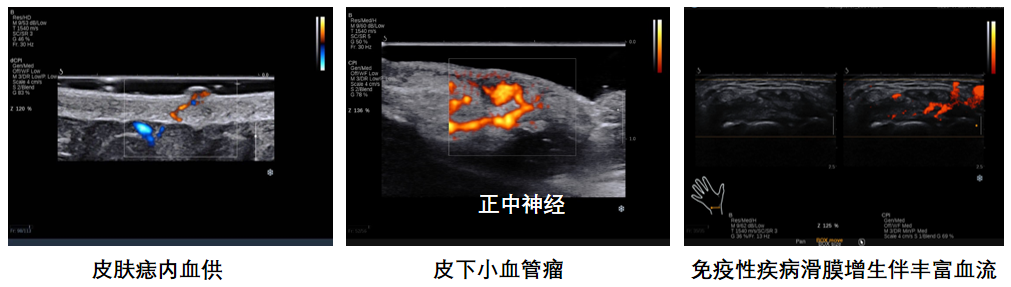

平面波超微细血流显像

彩色多普勒成像、3D壁滤波原理

血流敏感度明显提升,分辨率达微米级别

支持灰阶和微血流量同步测量、可测极低速血流的速度

多种模式,多数据定量评估。